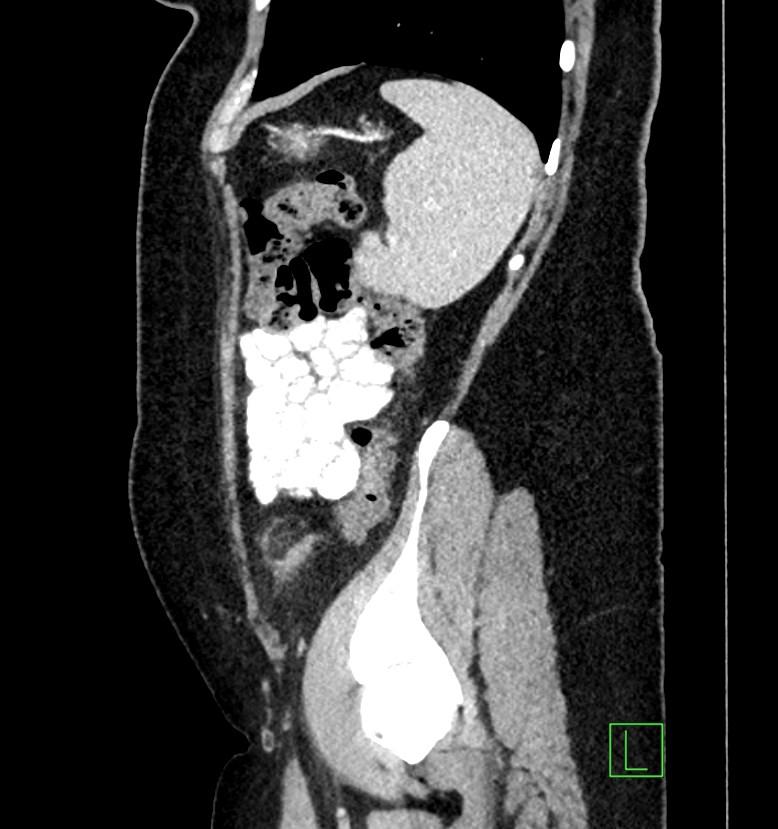

*50-year-old female present with left lower quadrant pain for 3 days.

Answer: Epiploic Appendagitis

MDCT images showed fatty density lesion adjacent to descending colon contains a characteristic hyperdense ring corresponding to thickened visceral peritoneal lining.

Epiploic appendages are small fatty peritoneal projections from the serosal surface of the colon. The inflammation of epiploic appendages can be due to torsion or venous occlusion. The disease is a self-limiting disease. Sonography and CT demonstrate an inflamed fatty lesion adjacent to the colon, including a characteristic hyperdense ring of thickened visceral peritoneal lining on CT [1].